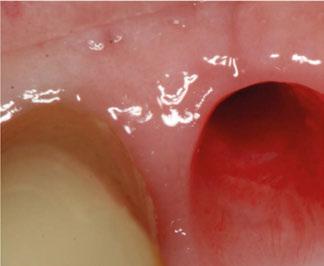

4 meses después de la cirugía la encía estaba completamente cicatrizada y las conexiones de los implantes tipo hexágono externo universal quedaron a nivel yuxtamucoso. En este caso no se requirió el empleo de pilares transepiteliales y las impresiones fueron tomadas

directamente a cabeza de implante para realizar una prótesis dentoalveolar de cerámica de 3 piezas, que equilibraran la oclusión y dieran soporte al labio y la mejilla (Figuras 14-17)